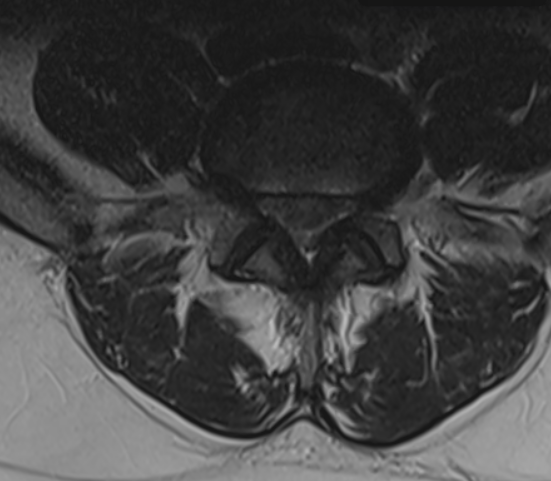

3. Cauda Equina Syndrome